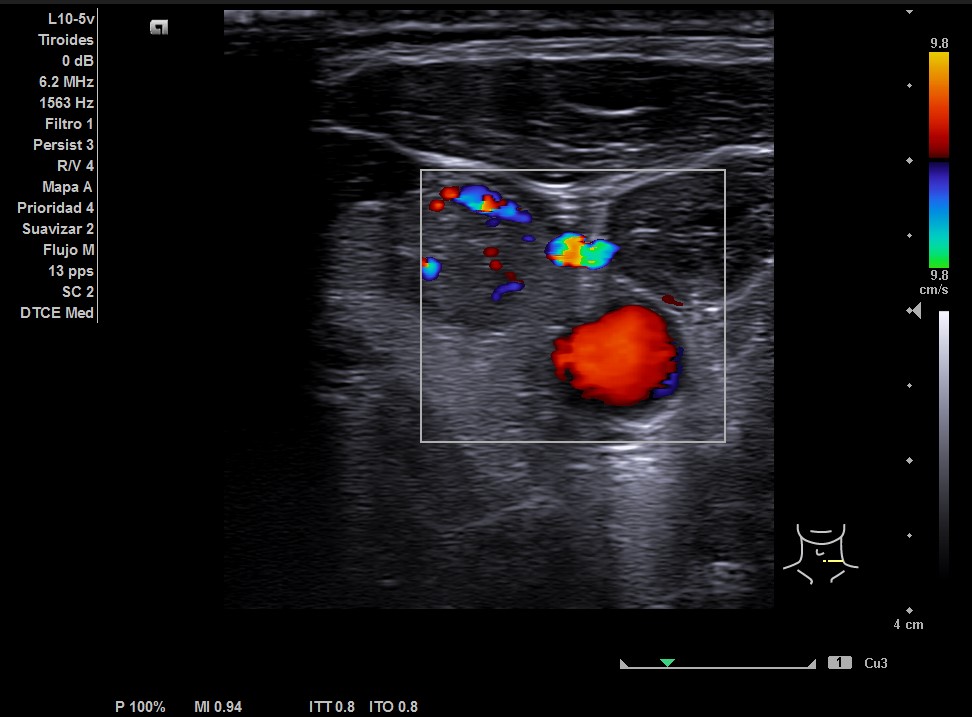

En la ecografía tiroidea se observa en LTI nódulo de 10 mm de bordes mal definidos, lobulado, mayormente sólido, más alto que ancho, isoecogénico, halo periférico hipoecoico, vascularización difusa, que sugiere TIRADS 5. Ausencia de flujo en Vena yugular interna izquierda, ensanchada, que sugiere trombosis yugular aguda o subaguda y junto a ella, posible conglomerado adenopático.